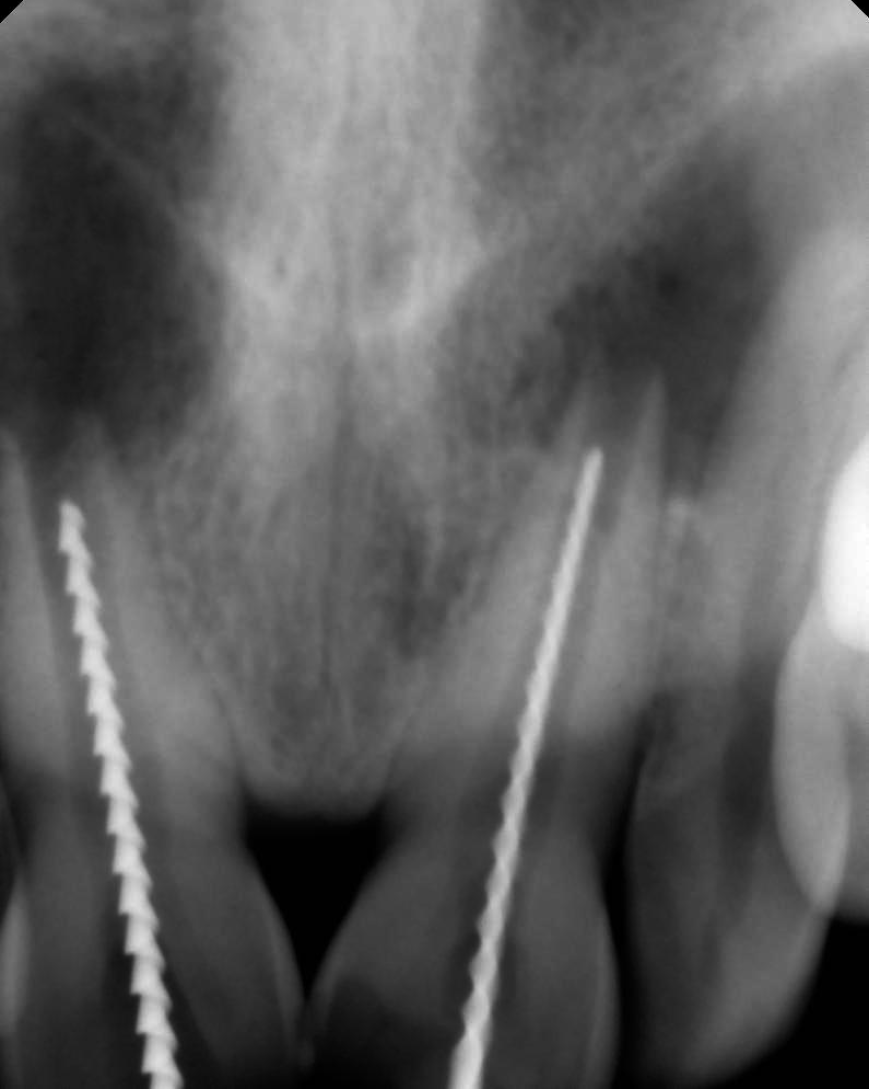

Figure 3 Shows the working length wrt 11 and 21.